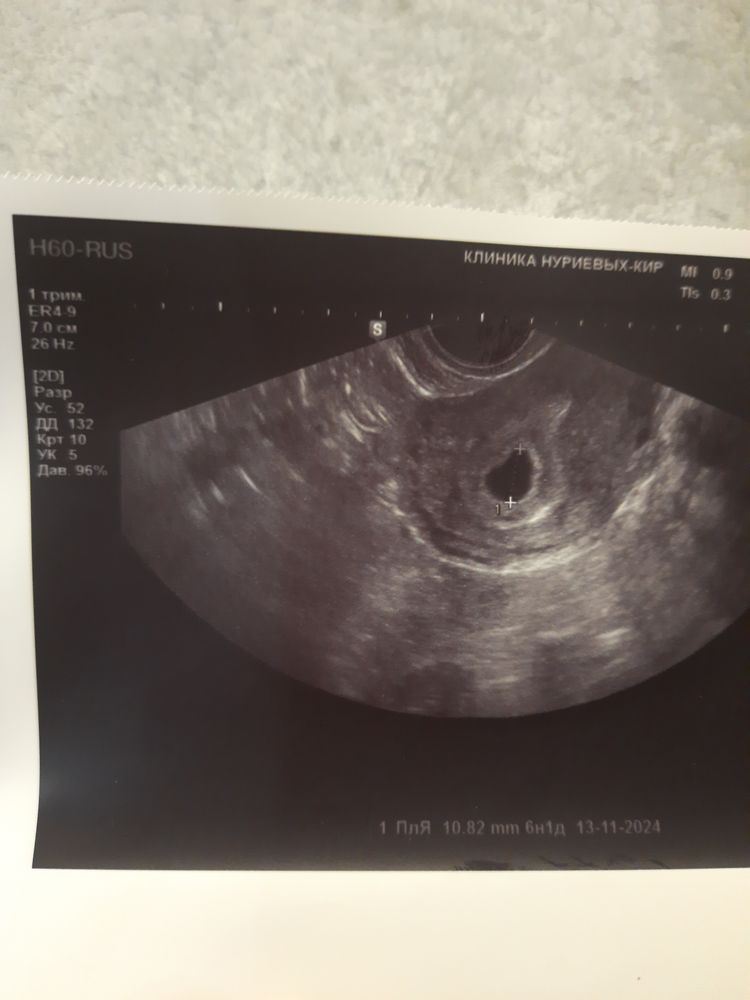

Снимок узи на 18 дпп

На фото вроде пока вообще пустое пя… через неск дней появятся уже жм и эмбрион

Миру Мир , просто на фото пустое пя как будто. Желаю вам чтобы все было хорошо . а у вас в роду много близнецов? Это прям должны сильно все звезды совпасть , чтобы подряд раздвоение было

Анна, да на снимке вообще ничего не видно конечно, но во время узи она прокомментировала что как будто видит 2 желточных мешка, или один желточный и эмбрион, в родк вообще нет ни у кого вообще ни с моей ни со стороны мужа близнецов, беременность эко криоперенос, при эко это частое явление, но так не хочется раздвоений больше, так это опасно, уже обна такая беременность у меня была.

Миа Мур, на узи я не увидела жм там написано только о пя🤷‍♀️ но подождите, а чего напугала? Двоих не хотите? Я б была на седьмом небе от счастья если б мой малыш поделился, но чуда не случилось , малыши у меня один